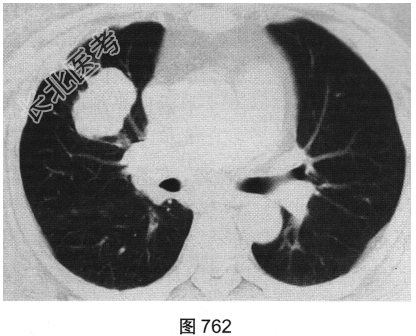

- 简答题2、患者行胸部CT检查,如图762、图763所示。胸部CT如图所示,超声心动图显示心功能降低,冠状动脉CTA除显示原支架内轻度狭窄外,未见其他异常。为明确病变性质,请问下一步应进行哪些检查?